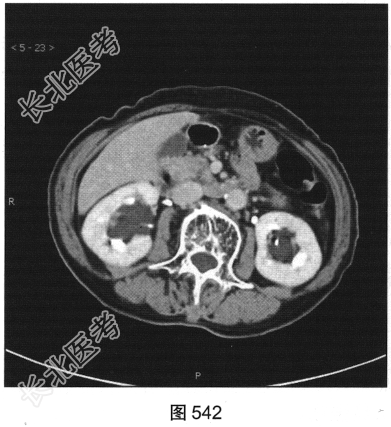

- 多项选择题3.[提示]CT平扫+增强(图538~图542)所见:双侧肾盂肾盏旁可见沿肾盂肾盏走行的多发囊样低密度灶, 未见明显强化。应考虑的鉴别诊断为( )

- 多项选择题4.综合影像表现,考虑肾盂旁囊肿的可能, 还应关注下列哪些情况( )

A、有无出血

B、有无感染

C、有无腹部其他脏器囊肿

D、肾实质受压情况

E、有无结石

F、有无并发肿瘤